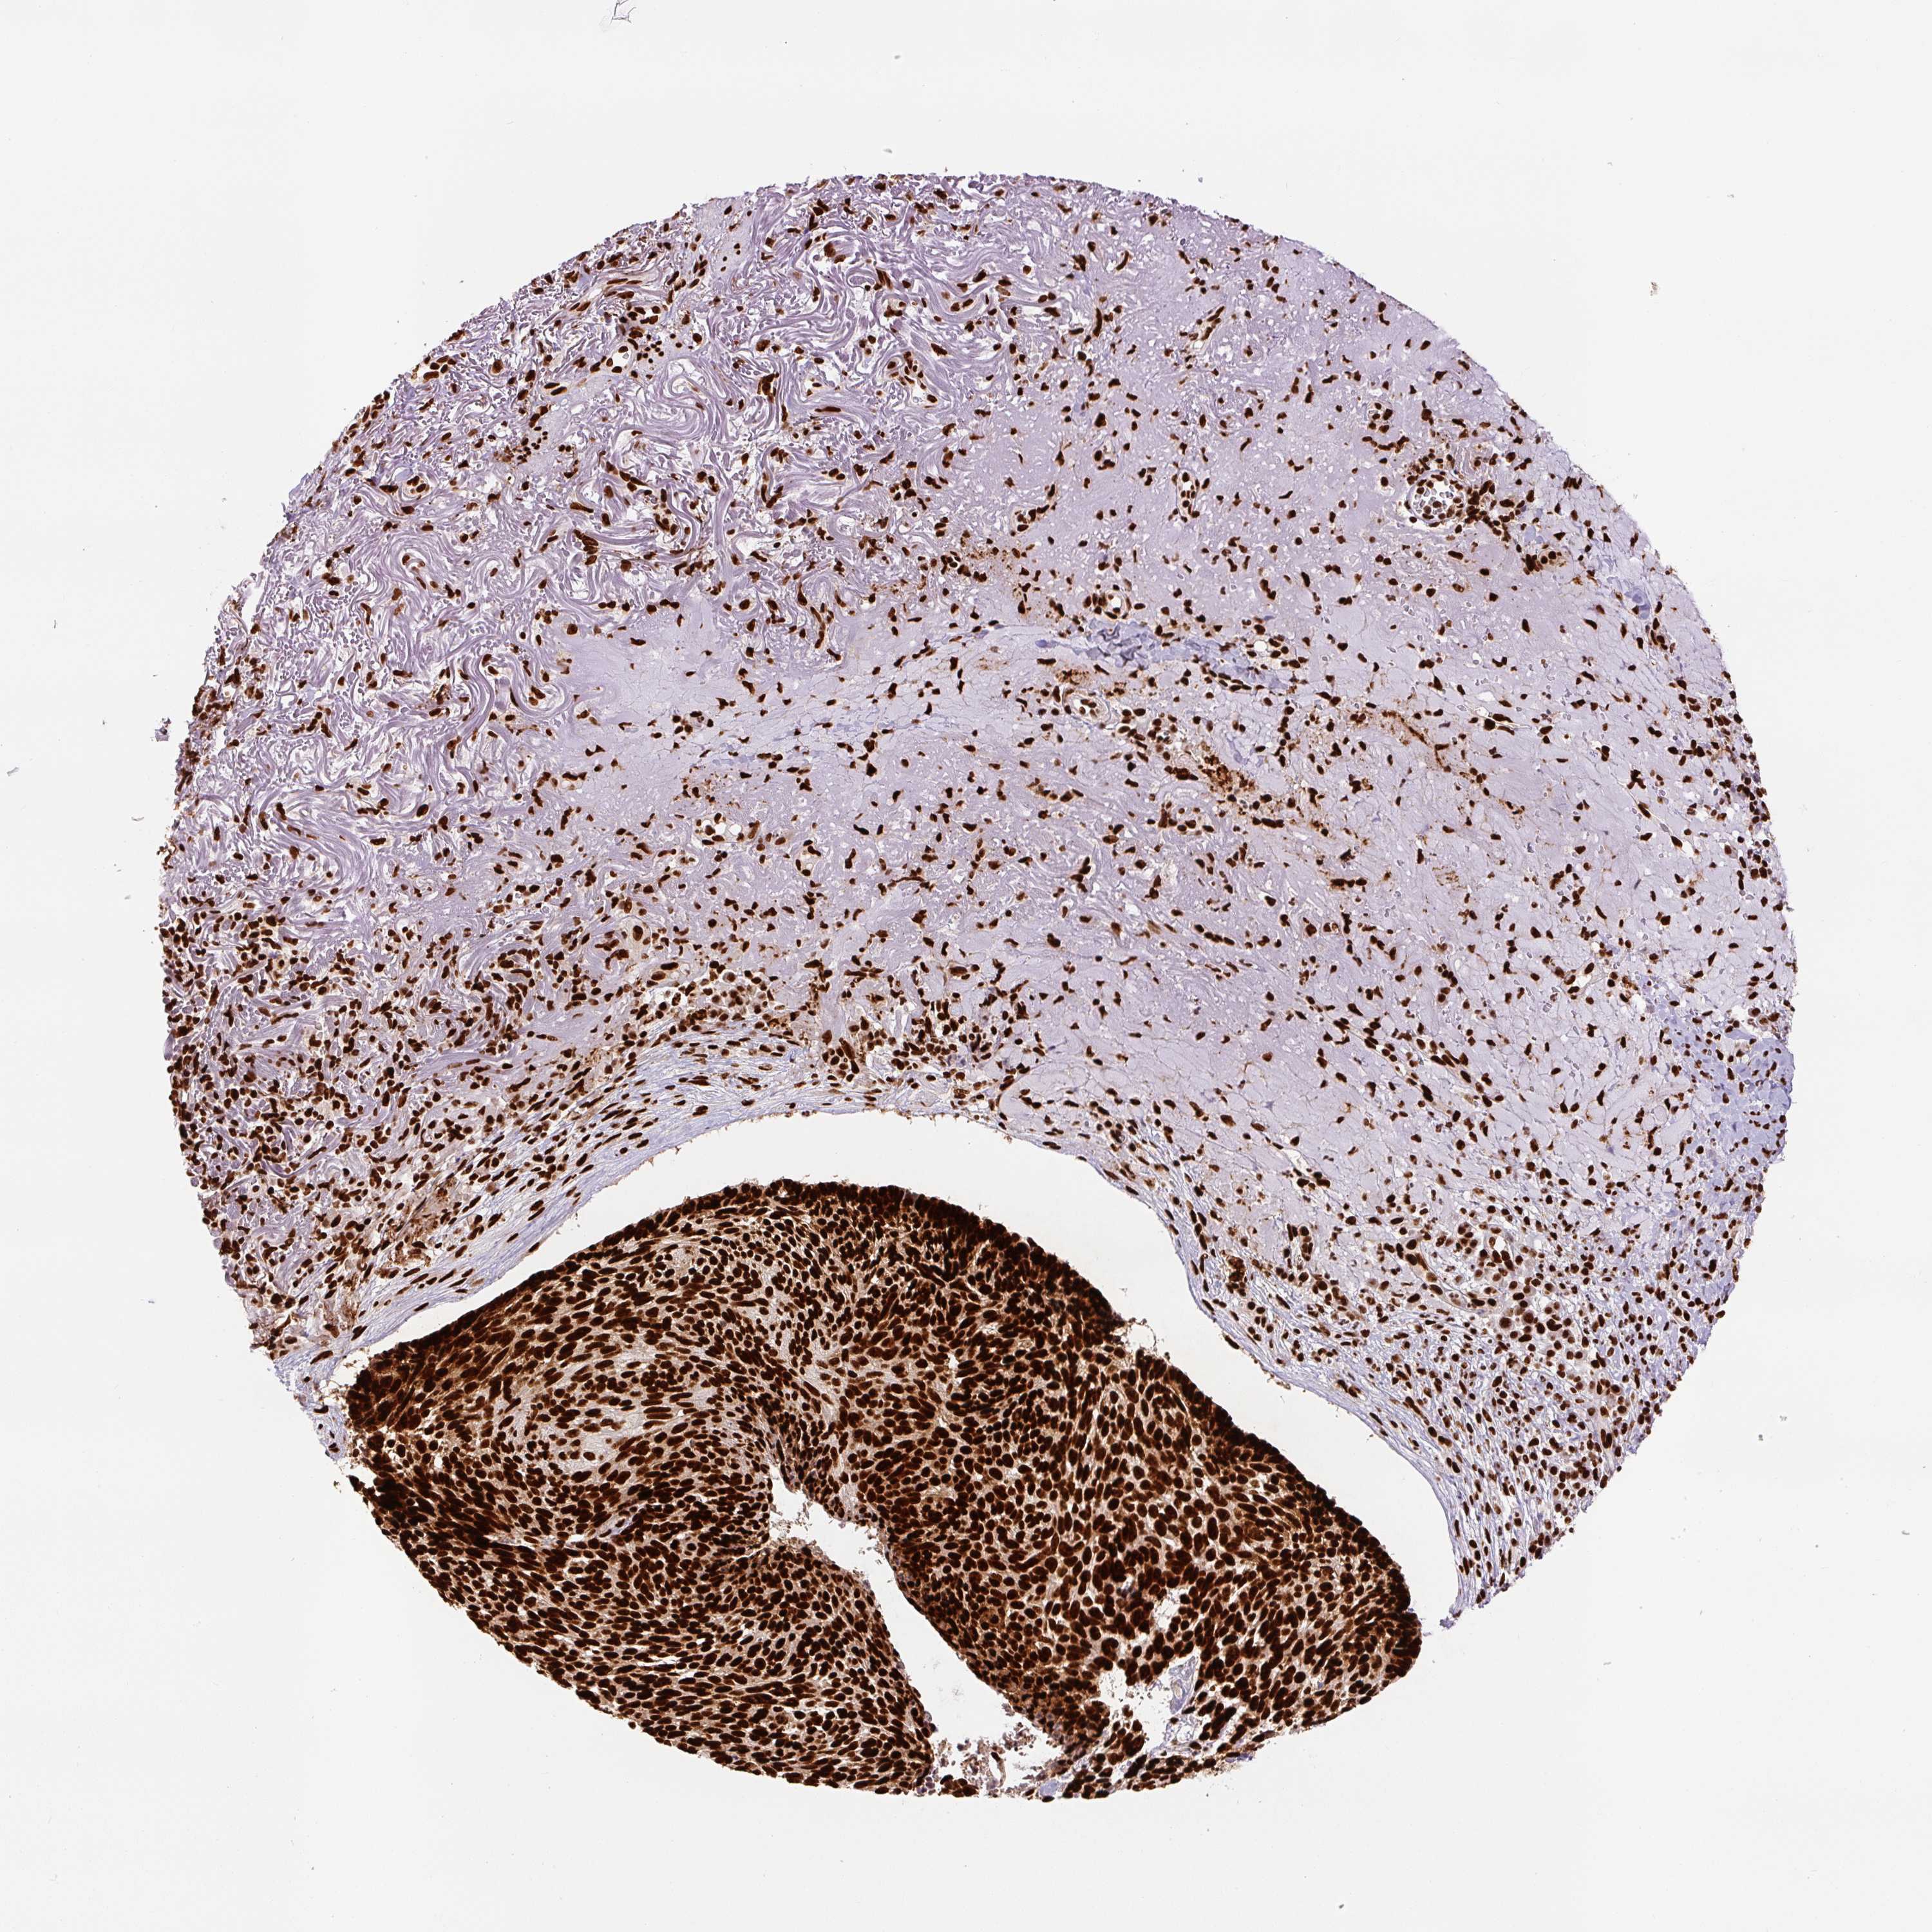

SKIN CANCER - Protein expressioni

A mouse-over function shows sample information and annotation data. Click on an image to view it in a full screen mode. Samples can be filtered based on level of antibody staining by selecting one or several of the following categories: high, medium, low and not detected. The assay and annotation is described here.

Antibody stainingi

Antibody staining in the annotated cell types in the current human tissue is reported as not detected, low, medium, or high, based on conventional immunohistochemistry profiling in selected tissues. This score is based on the combination of the staining intensity and fraction of stained cells.

Each image is clickable and will lead to virtual microscopy that enables deeper exploration of all samples and also displays staining intensity scores, fraction scores and subcellular localization as well as patient and tissue information for each sample.

Antibody HPA008784

Antibody CAB033036

Antibody CAB058691

Squamous cell carcinoma, NOS

Squamous cell carcinoma, metastatic, NOS

Basal cell carcinoma

Papilloma, NOS